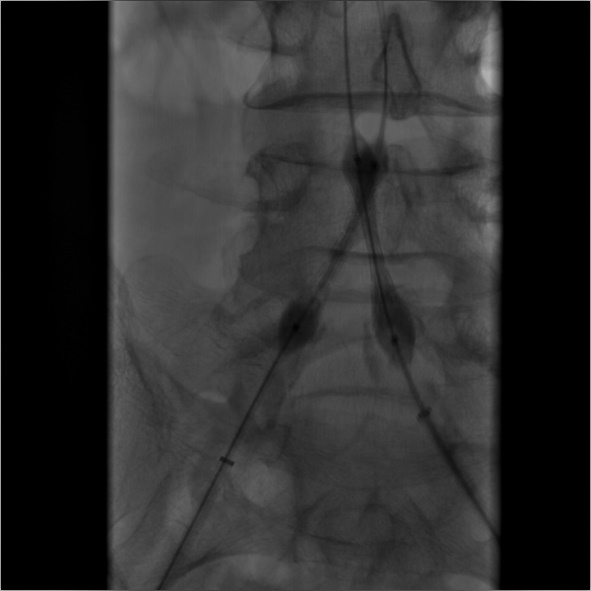

(3)建立右侧股总动脉逆行入路后,泥鳅导丝配合VER导管通过髂总动脉病变后,双侧入路交换为260cm加硬泥鳅导丝,随即透视监视下导入 8F*45cm长鞘至双侧髂外动脉近端;延右侧导丝进入INVETEC 5*40mm球囊行右侧髂总动脉狭窄病变预扩张。

导丝怎么扩【问术ASK】佟铸教授:双侧髂总动脉“对吻”球扩覆膜支架植入术_https://www.jmylbn.com_新闻资讯_第5张